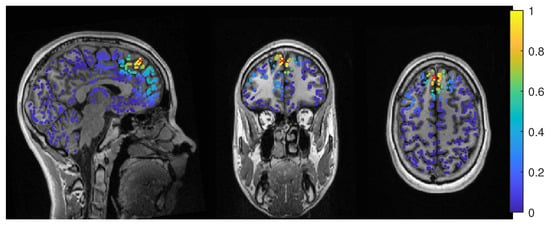

The average-based beamformer showed distance values below 5 mm for nearly all regularisation parameters and localized into the resection volume for both 6C and 3C head models when using a regularization parameter of 0.04. To better understand why results do not change smoothly with the regularization parameter, we present in Figure 4 the results for a parameter of 0.04, where the maximum point with maximum power of the localization is inside the resection, but the surrounding points are on the border with nearly the same power. With variations in the regularization, the maximum shifted around these points and gave a localization outside, which explains the changes observed in the distance to the resection volume. As Figure 3 also shows, the localization for the 6C model was inside the resection for all regularization values above 0.142. With a relative power relation value of close to 1, both models showed high uncertainty for regularization parameters above 0.1.

Except the cases of no regularization and average beamforming in the 6C head model, the differences of the evaluated methods in the distance to the resection volume for the MEG were overall lower than for the EEG. The event-related beamformer in both 6C and 3C head models showed localizations in the resection volume (localization distance of 0 mm) for the main part of evaluated regularization values. The 3C model’s localization distance increased slightly for the higher parameter value choices above 0.128. The 3C model’s power outside the resection was nearly the same as inside, resulting in a power relation close to 1, while the 6C model showed some certainty, with a power relation between 0.96 at low regularization values and 0.92 for high values. Both relations were not strongly affected by regularization. The localization of the 6C model at 0.05 regularization on the inside of the resection border is shown in Figure 5. While the maximum was inside the resection, the signal spread to the middle of the head to some degree.